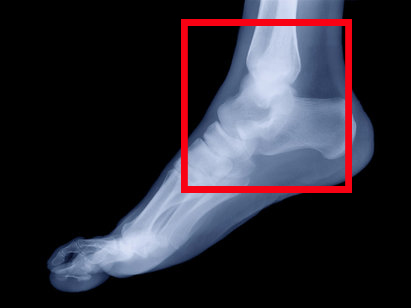

Диагноз ставят по клиническим симптомам, а подтверждают с помощью рентгенологического обследования. Лечение заключается во вправлении подвывиха, а при необходимости ‒ кратковременной иммобилизации (обездвиживании) сустава.

Из инструментальных методов исследования в диагностике подвывиха голеностопного сустава привлекаются:

- рентгенологическое обследование ‒ рентгенологические снимки делают в прямой и боковой проекциях (иногда ‒ в косой при необходимости проведения дифференциальной диагностики подвывиха голеностопного сустава с другими типами его повреждений). С помощью рентгенологических снимков оценивают степень смещения суставных поверхностей костей;